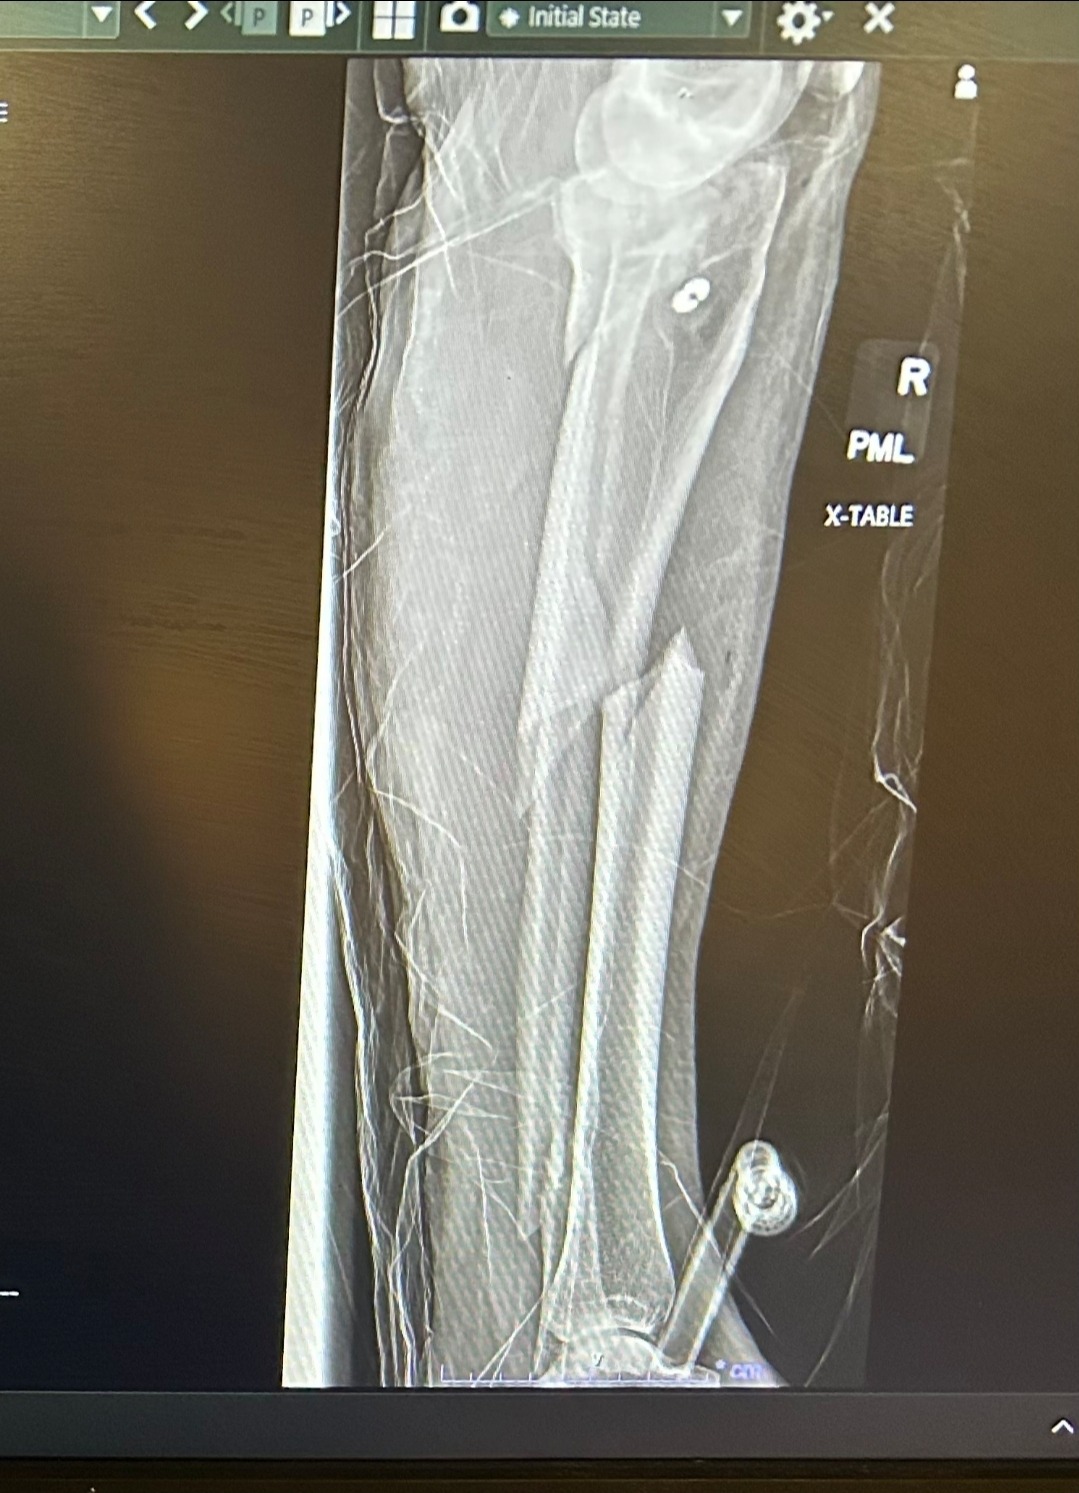

Earlier this year, Robin suffered a severe leg injury in a ski accident when she hit a rock hidden beneath the snow. The accident required multiple surgeries and a long, difficult recovery process. On top of that, she had already endured the heartbreaking loss of her boyfriend in a climbing accident last summer.